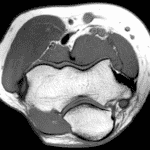

In the first Radsource Web Clinic of 2026, Dr. Ryan Schmidt describes an often overlooked cause of knee arthritis, and discusses MRI imaging findings that are clues to distinguishing the disease from other similar disorders.